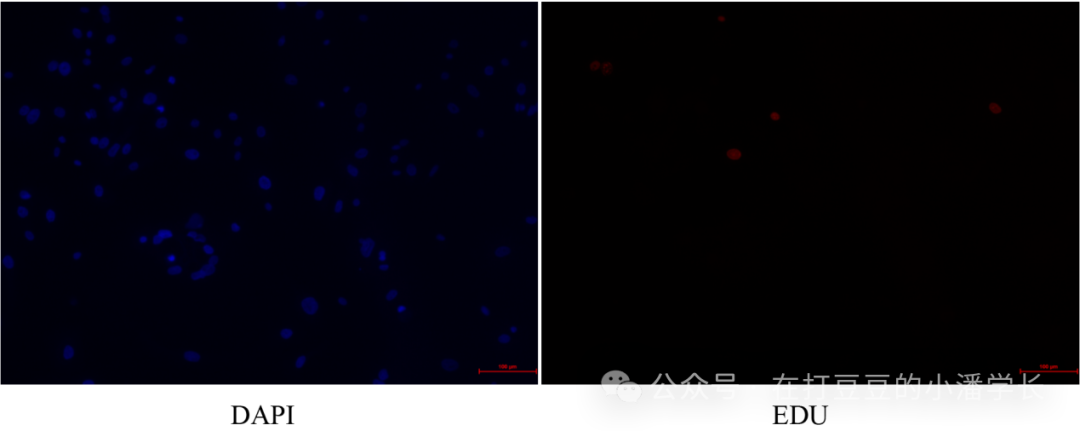

以下为本次处理的示例照片